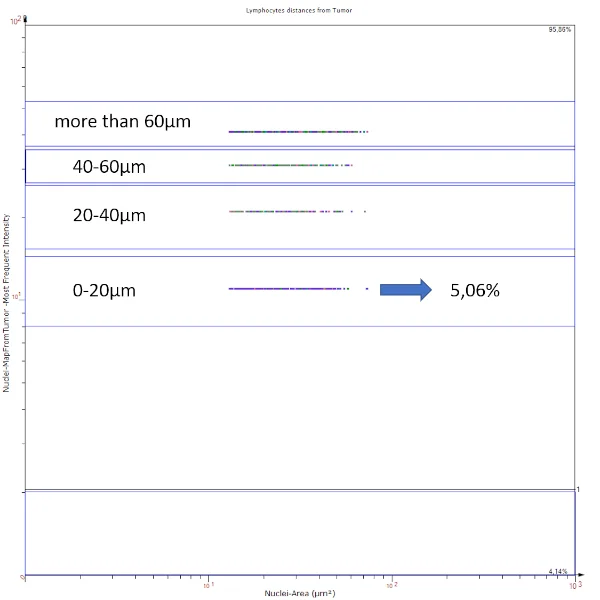

Apart from visual image analysis, StrataQuest outputs quantitative numbers. This way, it is possible to acquire and validate much more information. For example, StrataQuest can show how many cells are detected in each range: through the establishment of gates, 5.06% of CD3+ cells were found to be very close (in 20 µm range) to the epithelium.